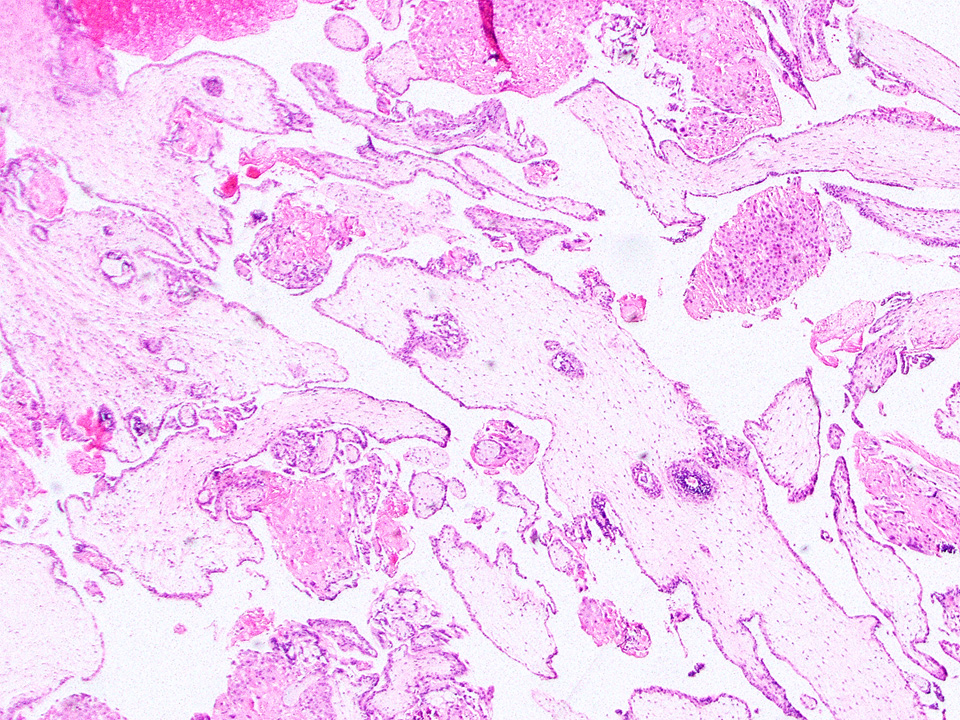

Microscopic (histologic) description

- Removed or passed products of conception may contain:

- Later first trimester chorionic sac (> 10 weeks): may exhibit loose fusion of amnion and chorion, a more collagenized chorion and stem villi, more distinct walls of fetal vessels and numerous villi with increasing demarcation between proximal and distal branches

- Spectrum of villous changes in immature chorionic villi following embryonic death (Placenta 2005;26:114):

- Collagenized avascular villi (villous sclerosis / fibrosis)

- Villous edema and sclerosis / fibrosis often coexist

- Placental implantation site:

- Extravillous trophoblast (EVT) within decidualized endometrium, visible maternal vascular remodeling, fibrinoid material in decidua, EVT within vascular wall or within vessel lumens

- Confirms intrauterine pregnancy even in the absence of chorionic villi

- Be careful with interpreting rare villi or syncytiotrophoblast in the absence of implantation site as this could indicate, although rarely, villous migration from a tubal pregnancy

- Other recognizable pathologies (intervillous / maternal space should be empty; if material is present, rule out these pathologies) (Hum Reprod 2007;22:313):

- Chronic histiocytic intervillositis (Malays J Pathol 2020;42:439)

- Massive perivillous fibrin deposition (look for extravillous trophoblast proliferation; otherwise, increased fibrin may be seen with embryonic demise secondary to prolonged retention in utero or secondary to medical abortions)

- Infectious etiologies: marked chronic lymphoplasmacytic or acute inflammation within the maternal vascular space or causing villitis (septic abortions - a critical value)

Microscopic (histologic) images

Contributed by Chrystalle Katte Carreon, M.D. and Drucilla J. Roberts, M.D.